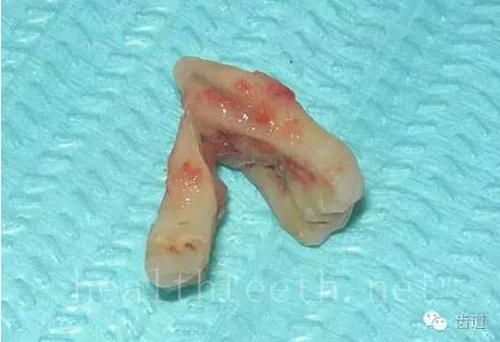

牙根折斷

59.jpg

烤瓷牙打樁修復(fù)后牙根折斷

60.jpg

外傷后牙齒的全脫位,應(yīng)該保留牙齒盡早做再植手術(shù)